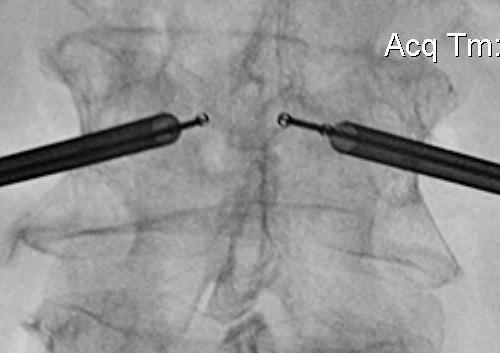

Technique

Insert a balloon first and inflate

- bilaterally into each pedicle

- will restore some anatomy

- then inject PMMA